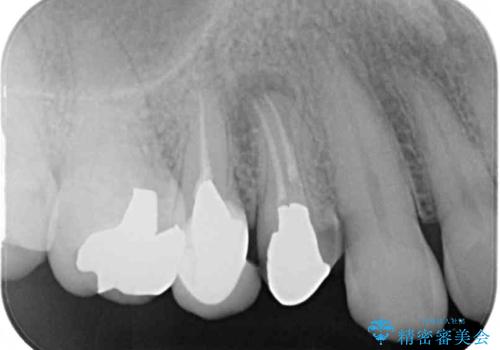

- クラウンが割れて治療を行っていたものの、途中で放置してしまったとのことで来院された患者様です。

根管治療を行った後に、ガラス系セラミッククラウンにて補綴することとしました。